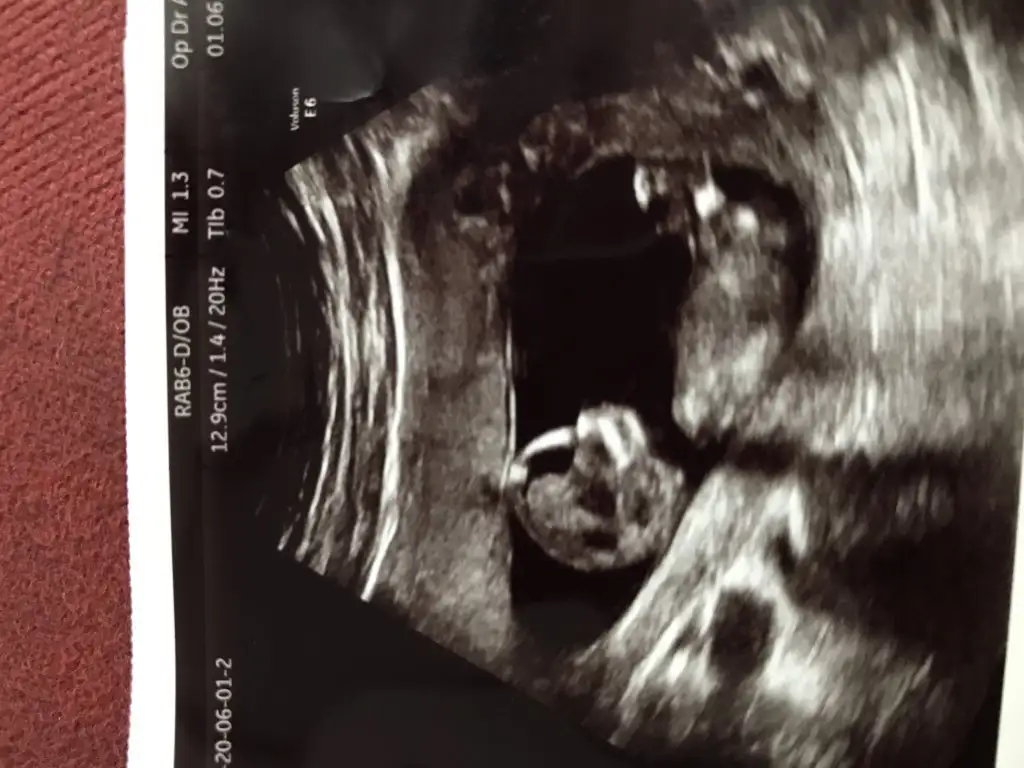

Rica etsem banada tahmin yaparmisiniz 8 haftada kiz demistiniz tekrar gondermemi istemistiniz dayanamadim bu usg 11 haftalik

Kız gibi net de değil kız sanki 12-13 olunca tekrar usg paylaşın